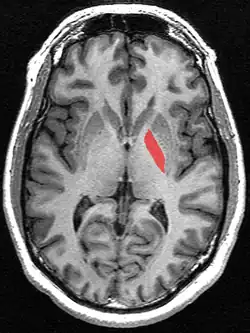

Globus pallidus (in red) shown within the brain

Transverse section of the globus pallidus from a structural MR image.